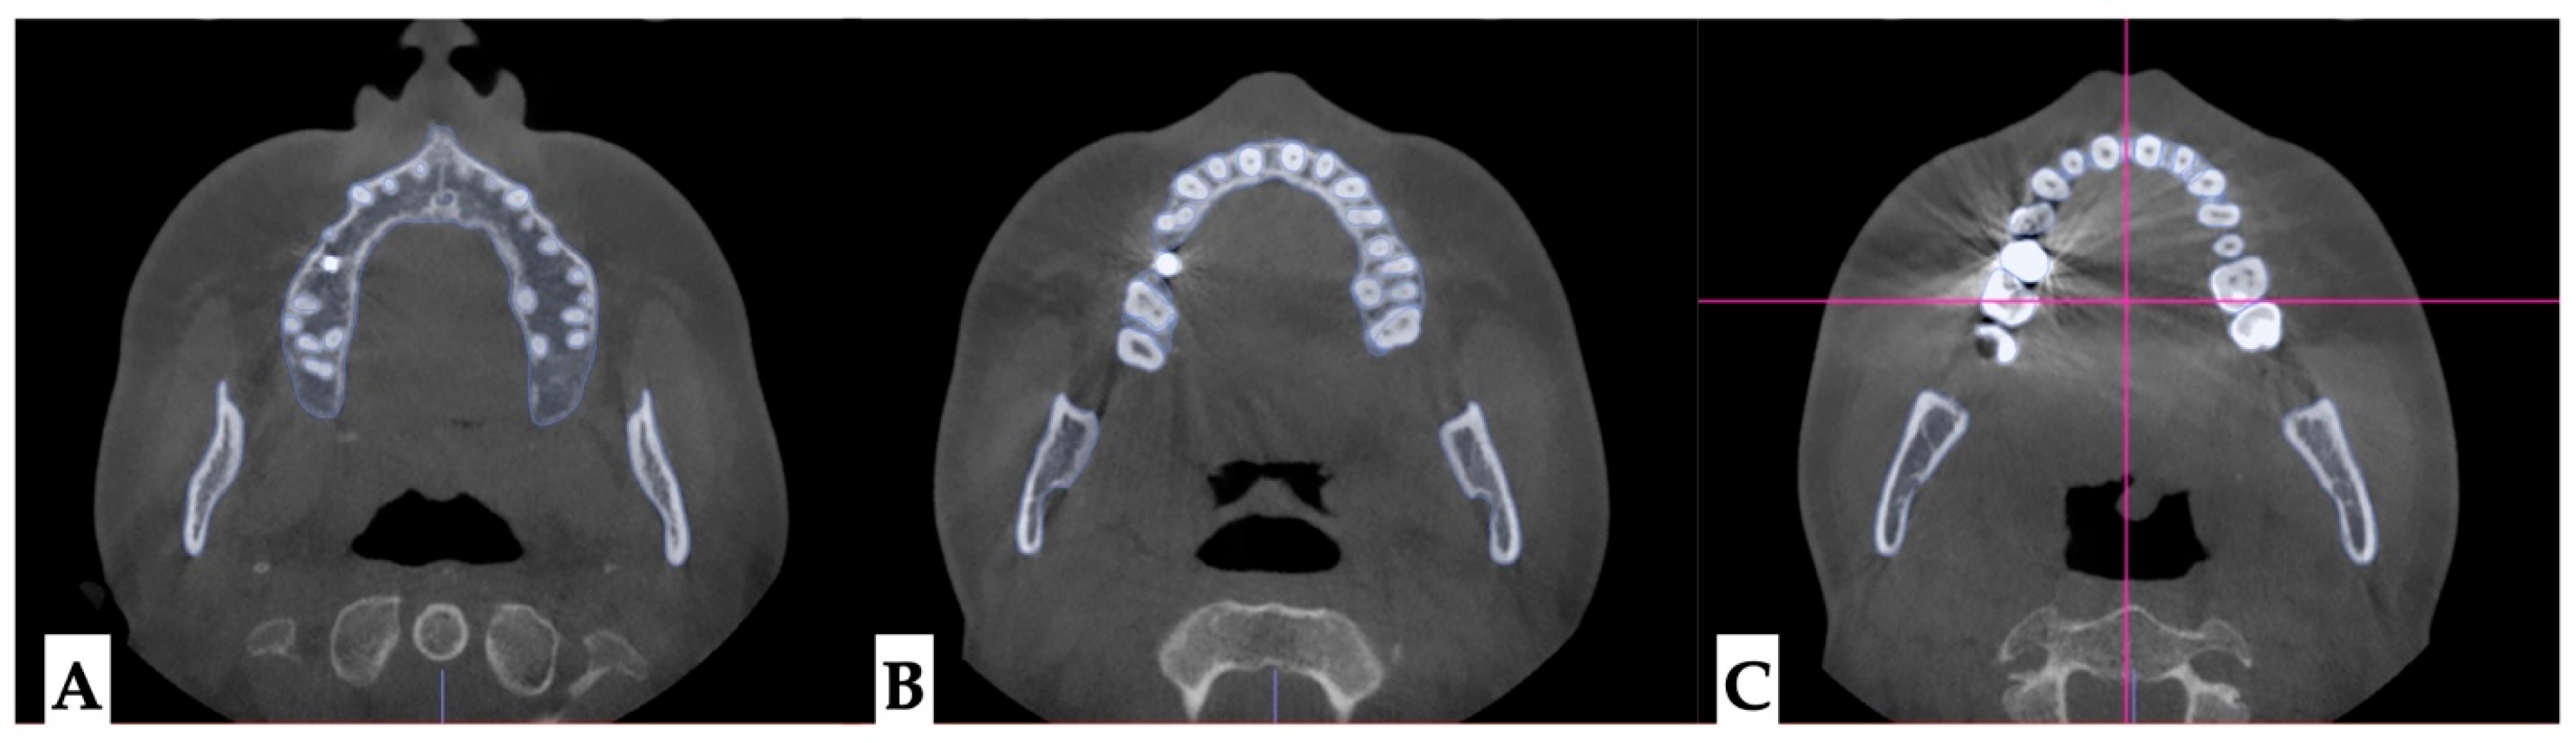

2.3.2. Design of 3D Surgical Guide

2.3.3. Osteotomy Planning and Appliance Design

2.3.4. Postoperative Assessment, Outcome Analysis, and Asymmetry Correction